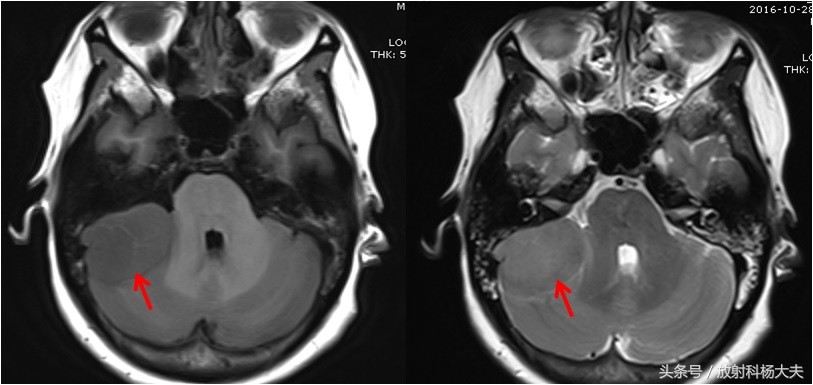

但有一点请大家注意,这个征象一定要考增强扫描才能看到,如下图,为本例的平扫图像,是无法准确观察脑膜尾征的。